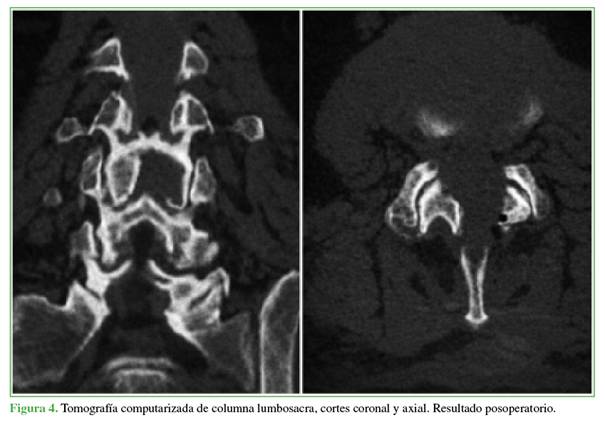

Los hallazgos fueron consistentes con un quiste sinovial facetario hemorrágico. Dados la presentación aguda con déficit neurológico motor progresivo y el severo compromiso radicular, el paciente fue sometido de urgencia a una descompresión. El objetivo fue aliviar la compresión neural, revertir el déficit motor y permitir una recuperación funcional rápida, minimizando la invasividad. Se optó por una descompresión endoscópica uniportal interlaminar posterior, utilizando un abordaje contralateral (izquierdo) y la técnica “over the top” (por encima del saco dural) para resecar el quiste de forma segura y completa (Figuras 2-5).